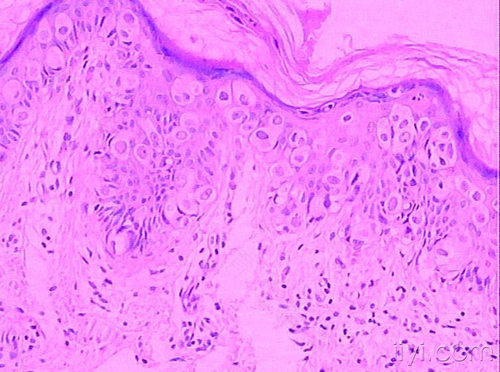

有些患者在日常生活中会发现自己外阴部位长出突出的东西,而且有时候会是几个突出软软的囊肿。其实这个问题就是临床中所谓的外阴皮下囊肿,那么外阴皮下囊肿到底是由什么原因造成的呢?

2、其他因素。有些患者自身患有糖尿病、尿瘘病、肠道囊肿等疾病时,也会容易对外阴处产生一定刺激,从而诱发外阴皮下囊肿的问题。要具体明确是哪一种原因引起的,还应该去当地医院进行详细检查,分析病原体之后才可进一步明确。

3、致病因素。有些女性在日常生活中可能因为某些原因而导致混合性感染,在这种状态下也很容易诱发外阴皮下囊肿的问题,比如常见的致病菌有链球菌、葡萄球菌、大肠杆菌以及其他类型的致病菌等等。